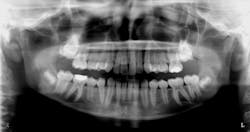

Diagnosis: Ectopic third molar

In this case, the ectopic third molar was removed surgically, the second molar luxated lightly to determine if ankylosed, and then the tooth was allowed to erupt on its own.

This case is currently being followed. If the tooth fails to erupt on its own and becomes ankylosed, most likely it will need to be removed by an oral surgeon.